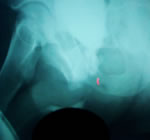

- Обзорная и экскреторная урография - функция верхних

мочевых путей не нарушена, камень мочевого пузыря,

деформация костей таза.

- Восходящая уретрография - подозрение на стриктуру

перепончатого отдела уретры.

- Микционная уретрография - дилятация простатического

отдела перепончатой уретры